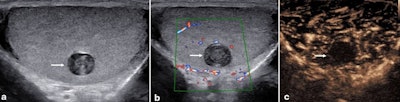

Epidermoid cyst. A 19-year-old man with a history of nonspecific pain was found on ultrasound (a) to have an incidental lesion in the left testis (arrow) with features suggesting an epidermoid cyst. There was no color Doppler (b) signal in the lesion (arrow). On the contrast-enhanced ultrasound (c) exam, there was no vascularity within the lesion (arrow).